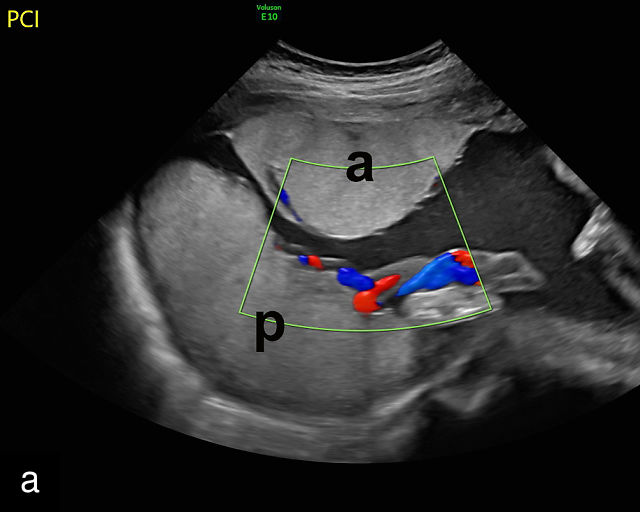

4

Accessory placental lobes. (a) Color Doppler transabdominal ultrasound image depicting a bilobed placenta with an anterior (a) and posterior (p) lobe, into which the cord inserts. (b) Grayscale ultrasound with color flow Doppler showing a bilobed placenta with anterior (a) and posterior (p) lobes. Color flow Doppler shows unprotected fetal vessels traversing the membranes between the lobes (arrow). (c) Grayscale ultrasound showing a bilobed placenta with anterior (a) and posterior (p) lobes.

The sonographic features of a bilobed or succenturiate-lobed placenta include the presence of two distinct placental masses, typically one anterior and the other posterior, which may vary in size or be of equal size.21,22,23,24,26,31,32,33 These masses are connected by blood vessels, which can be visualized using color flow Doppler (Figure 4).28